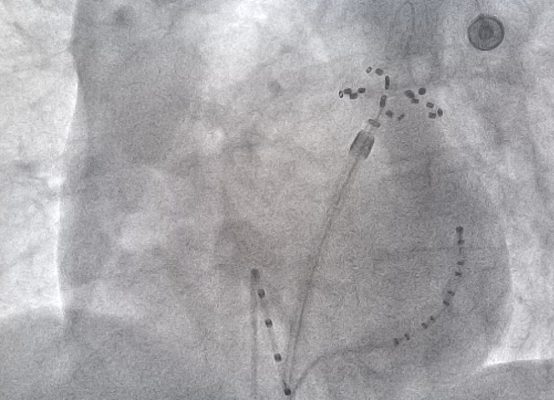

X线下FARAPULSE脉冲消融导管的形态:花瓣状